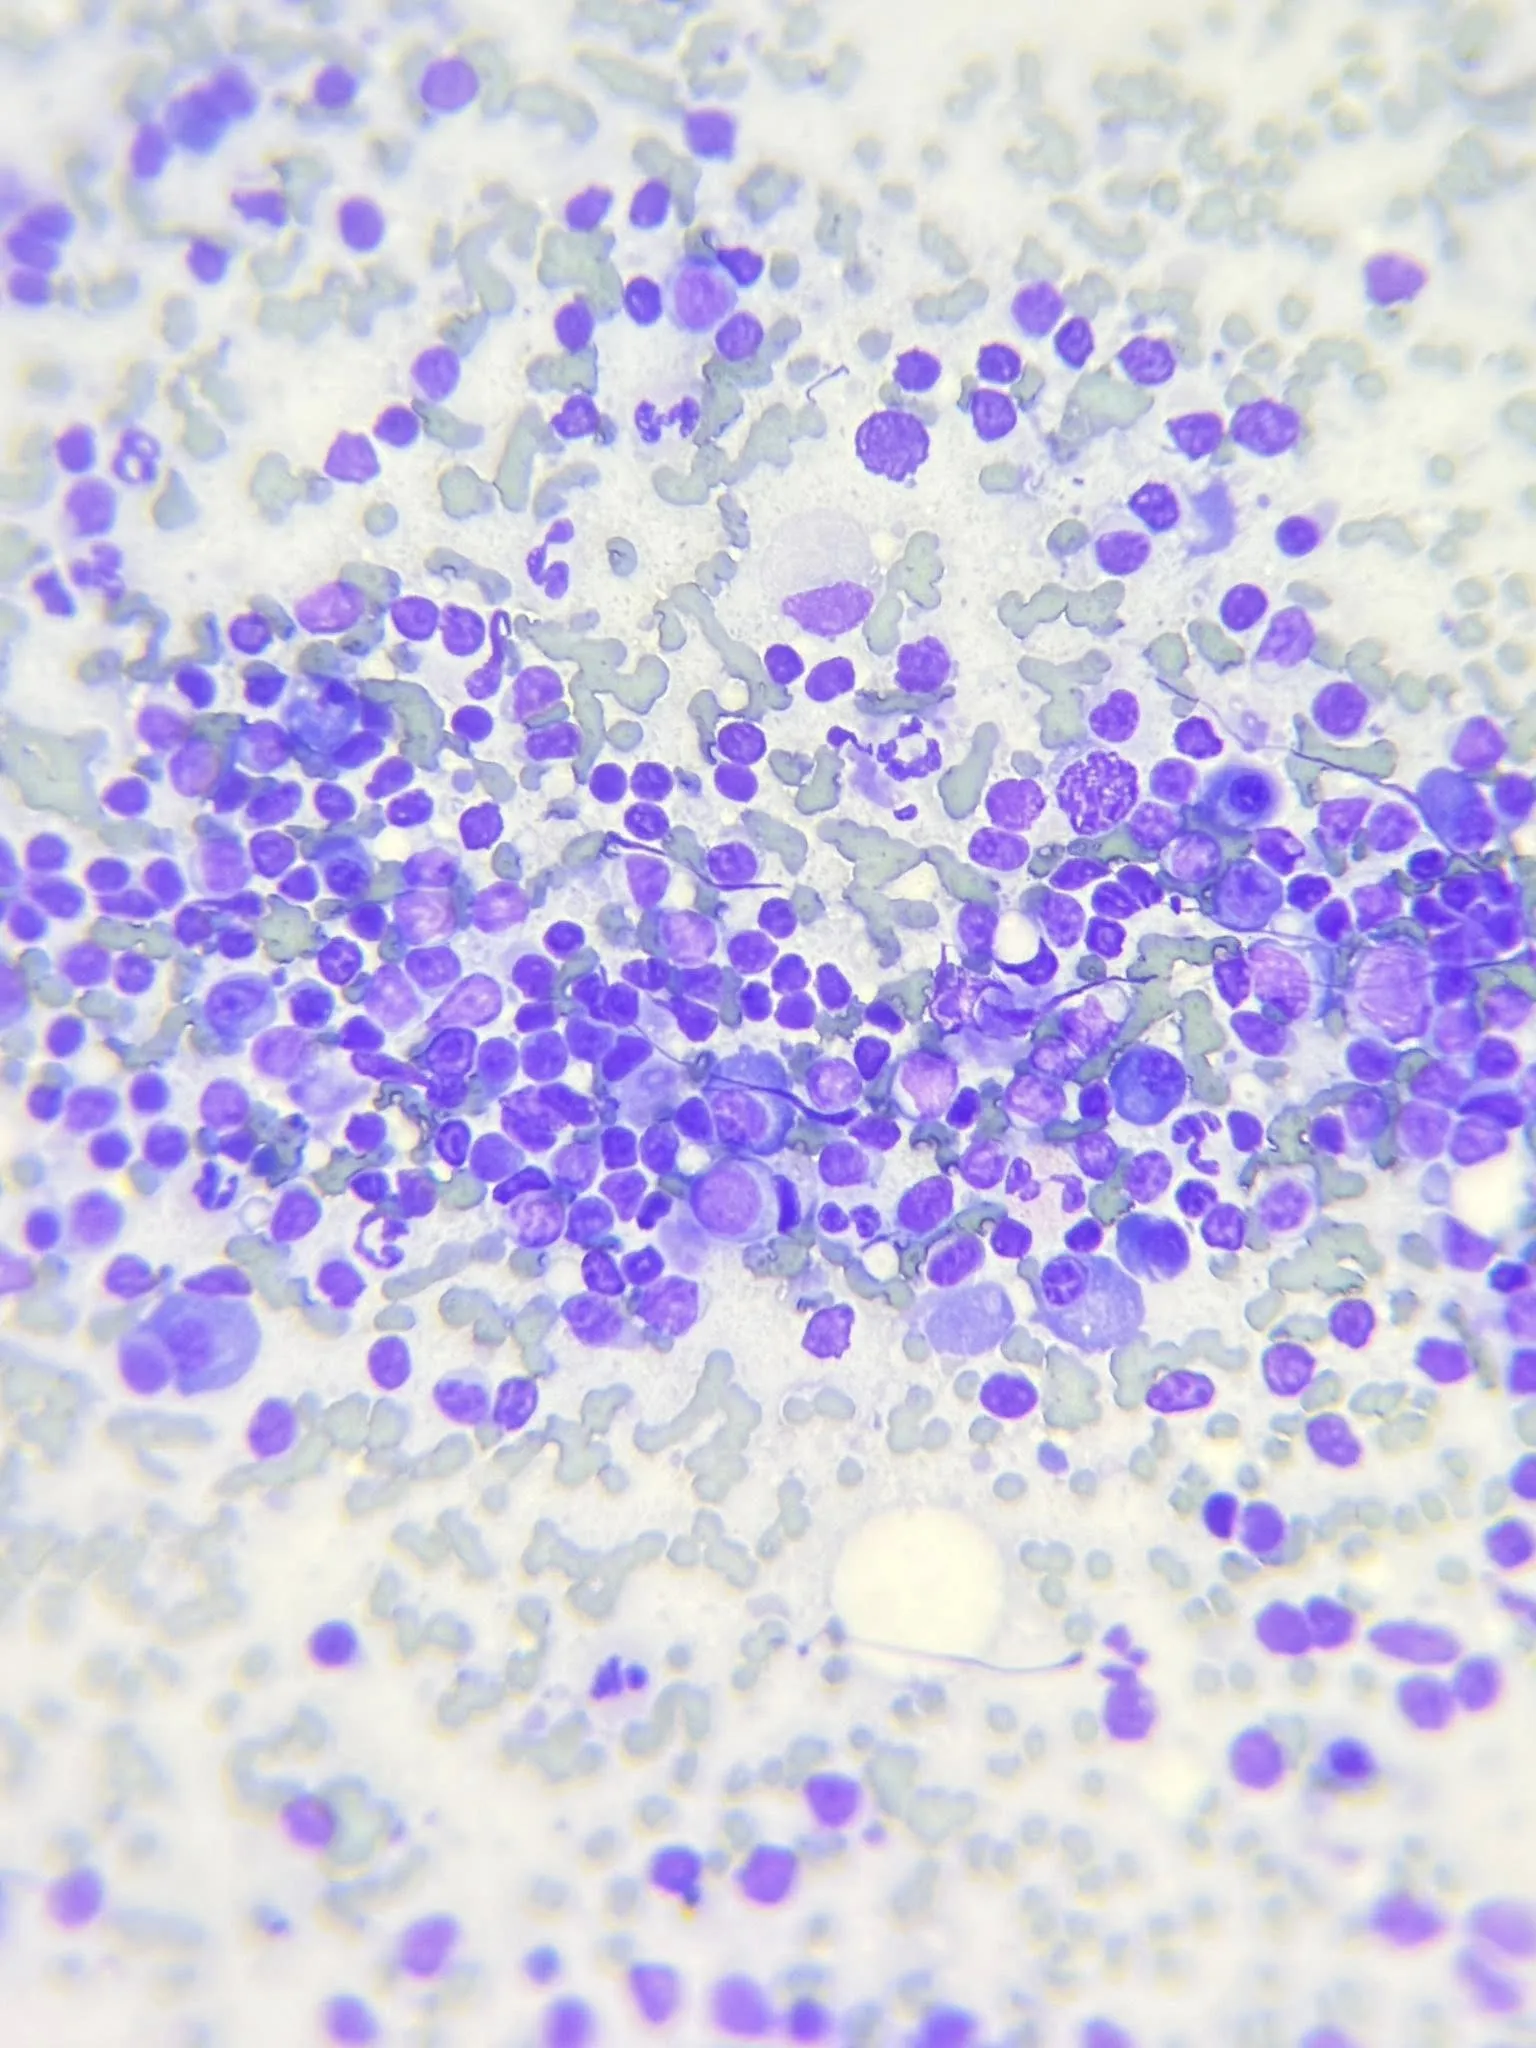

✔️ 細胞學分析顯示非惡性腫瘤 (為化膿性肉芽腫性炎症)

✔️ 細胞構成複雜,與淋巴癌不符(診斷增生性淋巴腺炎)

✔️ 細胞學分析顯示非惡性腫瘤 (為化膿性肉芽腫性炎症)

✔️ 細胞構成複雜,與淋巴癌不符(診斷增生性淋巴腺炎)